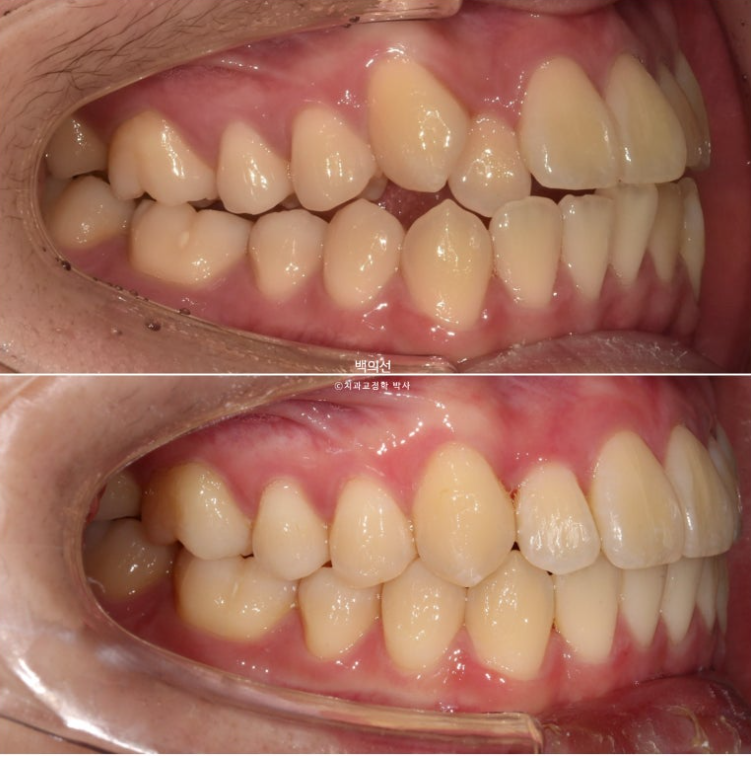

전 후 비교 보겠습니다.

24.04~25.07

덧니와 반대교합은 해소가 되었습니다.

교합은 좋고 양쪽 다 1급 교합관계를 보입니다.